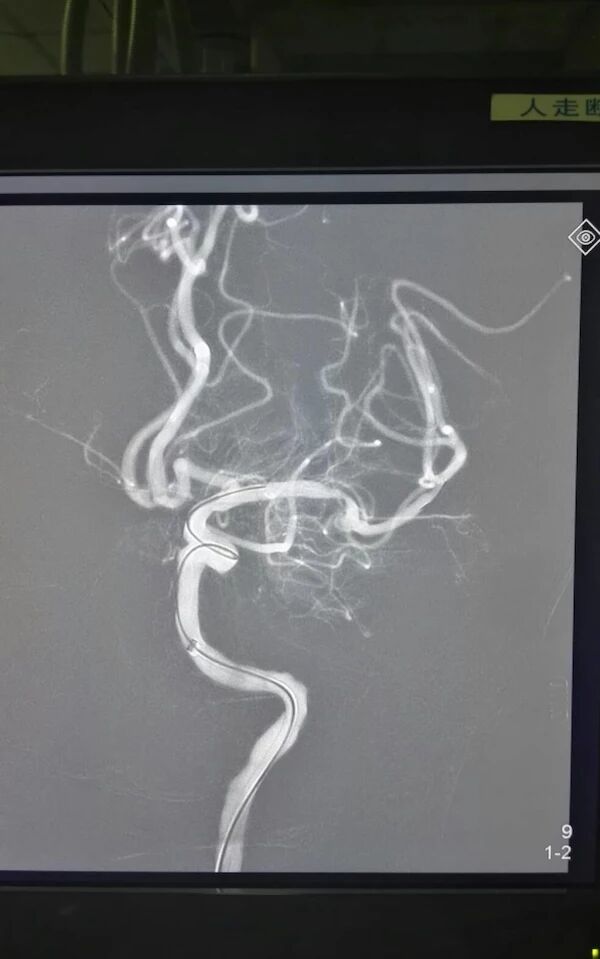

术前脑血管造影显示左侧大脑中动脉急性闭塞,代偿不佳

微导管通过血栓后造影显示远端血管通畅

使用ReviveSE取栓,一次成功

术后观察30分钟,达到2b级血流,近分叉部的狭窄二期处理,细小下干未进一步取栓!回病房给予替洛菲班和复合量双抗治疗